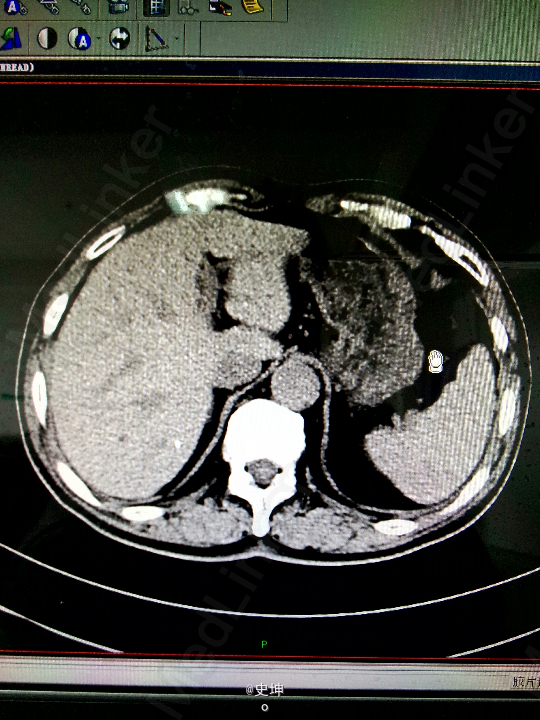

男,80岁 主诉:血尿2月余,检查发现膀胱肿瘤5天 现病史:患者自诉2月前出现一次肉眼血尿,未予特殊处理后好转,半月前患者再次出现无痛血尿,伴尿频,5天前血尿加重,与当地医院检查,发现“膀胱肿瘤”,未予特殊治疗,。今为求进一步治疗,来我科就诊。起病以来,患者精神、饮食、睡眠可,体力体重无改变。

查体:T:38.0℃,P:84次/分,R:20次/分,BP:150/80mmHg,余查体无异常。 X线:可见膀胱充盈缺损,膀胱壁僵硬不规则。 CT:1、膀胱右后壁贱菜花样软组织团块影。2、所及肝脏多发小囊肿,肝内散在小钙化灶或胆管结石。